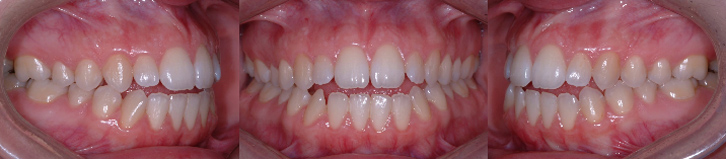

Fille de 12 ans avec chevauchement et arcade supérieure étroite. (A) Malocclusion avant le traitement. (B) Après le traitement sans extractions, l’arcade supérieure est plus large et le chevauchement dentaire est éliminé.